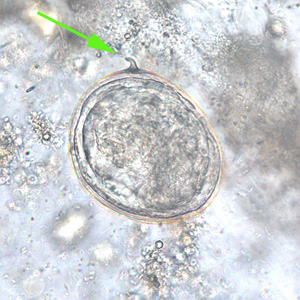

Case #235 – September, 2008

A 25-year-old man returned from three months of studying abroad in southeast Asia. Countries he visited during his studies included the Philippines, Indonesia and Thailand. Shortly after returning to the United States, he presented to his health care provider with abdominal pain, cramps and diarrhea. Due to the travel history, a routine ova and parasite (O&P) examination was performed on the patient’s stool. Objects A–F show objects observed in the formalin-concentrated stool specimen. All images were captured at 400x magnification. The object in Figure A measured approximately 70 micrometers long by 47 micrometers wide and was seen in large numbers. The objects in Figures B and E measured approximately 75 micrometers long by 60 micrometers wide and were seen in moderate numbers. The object in Figure C measured approximately 67 micrometers long by 38 micrometers wide and was seen in moderate numbers. The objects in Figures D and F measured approximately 25 micrometers long by 13 micrometers wide and were seen in rare numbers. What is your diagnosis? Based on what criteria?

Figure B

Figure E